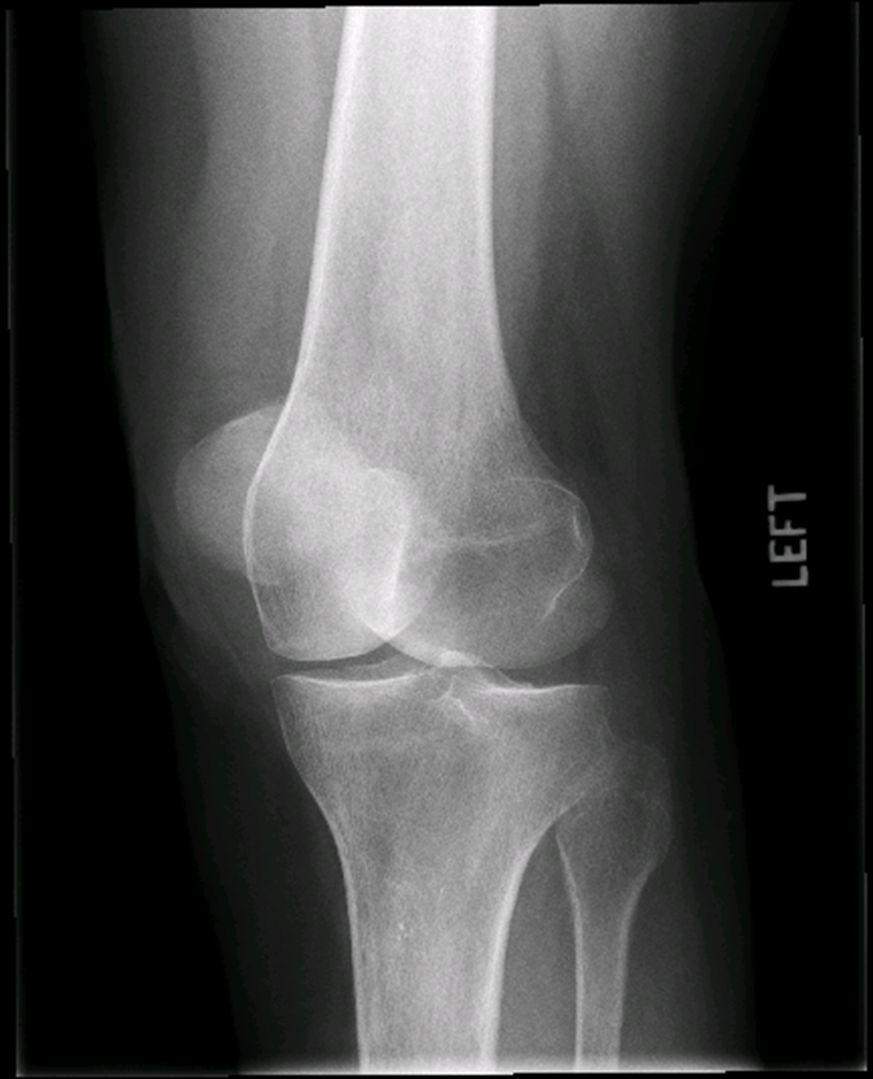

osteoarthritis (degenerative joint disease)

generalized disorder pathologically characterized by loss of joint cartilage & reactive new bone formation

traumatic, stress to joint

what is the casue of osteoarthritis?

advance stage → subtractive disease

pt w/ osteoarthritis

what is this image?